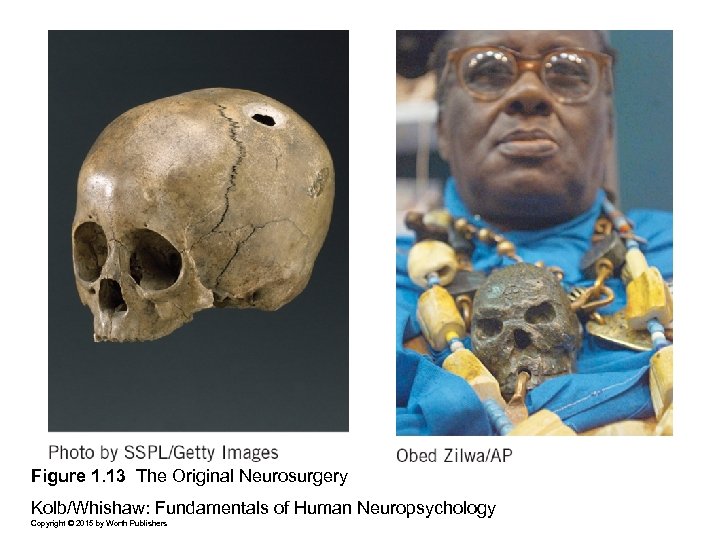

Figure 1. 13 The Original Neurosurgery Kolb/Whishaw: Fundamentals of Human Neuropsychology Copyright © 2015 by Worth Publishers